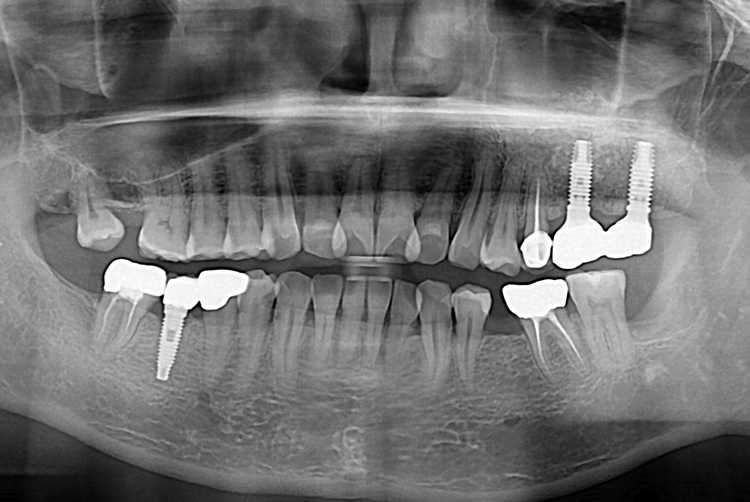

[임플란트] 어금니 임플란트

치료후 : 2017-09-22

세종치과는 많은 환자와 다양한 케이스를 바탕으로

항상 편안한 임플란트 수술을 제공하고자 노력하고,

오래동안 튼튼히 쓸 수 있는 임플란트 수술을 가장 큰 목표로 삼고 있습니다.